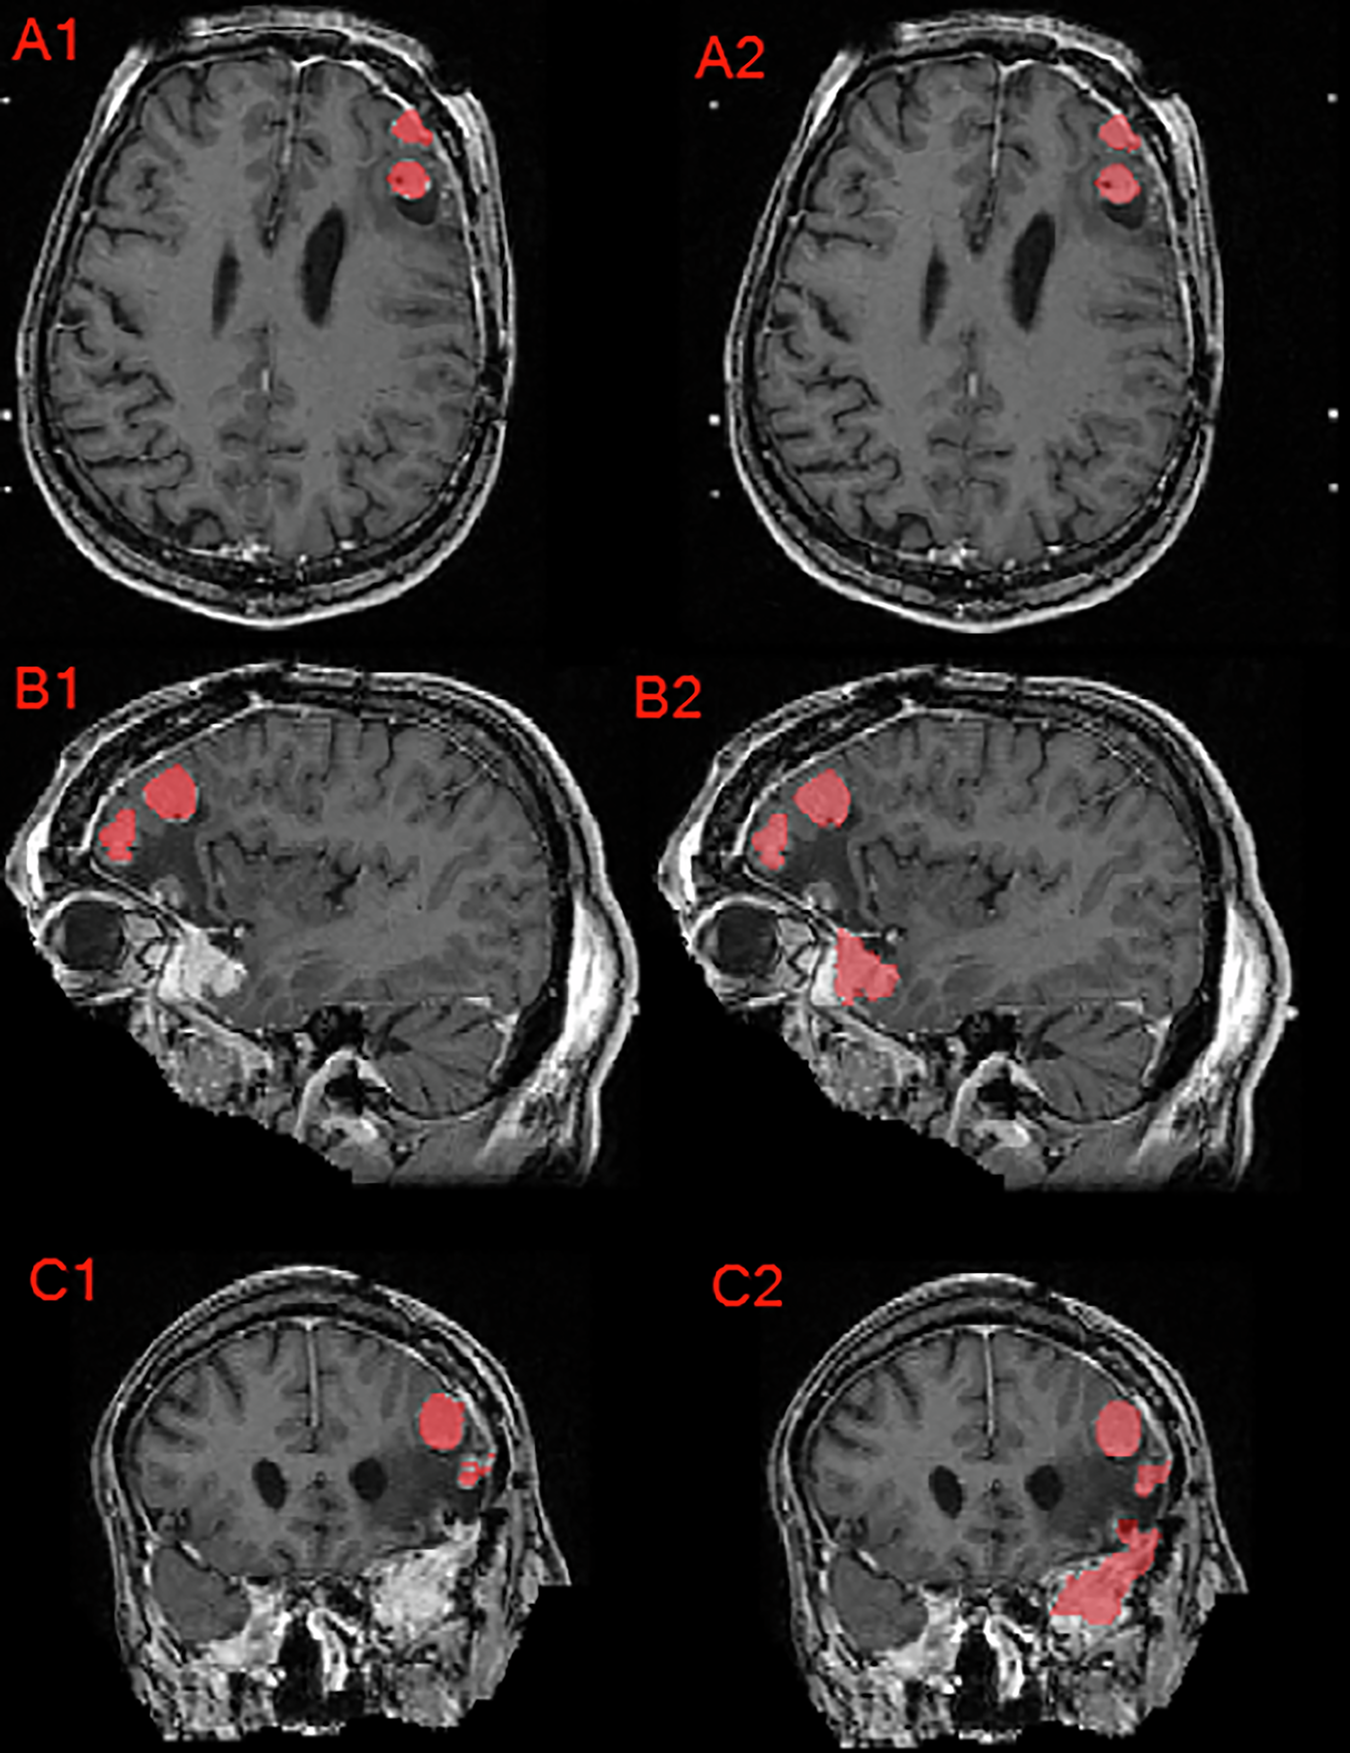

Fig. 8

From: The 2024 Brain Tumor Segmentation Challenge Meningioma Radiotherapy (BraTS-MEN-RT) dataset

Axial, sagittal, and coronal brain MRI of a patient with multiple meningioma demonstrating the difference between the provided institution’s GTV as seen in panels A1, B1, and C1 compared to the manually revised target label as seen in panels A2, B2, and C2. Note that this case’s corrections involved inclusion of additional meningioma, correction of label edges, and inter-axial slice label smoothening.